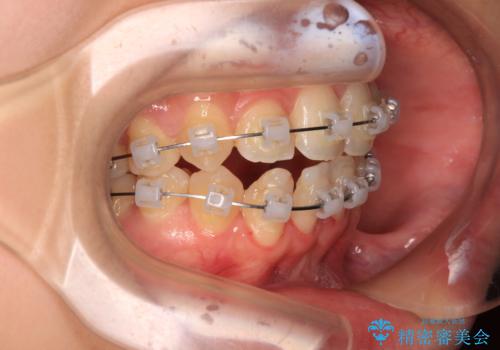

後戻りの再矯正 ワイヤー装置でデコボコと隙間を改善

- クリアブラケット

- 学生時代の抜歯矯正の後戻りが気になり、再矯正を希望して来院された患者様です。

マウスピース矯正は継続する自信がなく、気になるところを短期間で改善したいとのことで、ワイヤー装置にて矯正治療を行うこととしました。

詰め物で隠していた下顎前歯の隙間は、歯軸を改善することで詰め物を除去しても隙間が目立たなくなりました。

まだ改善したいところはありましたが、患者様自身は大変満足されたとのことで、治療を終えることとなりました。